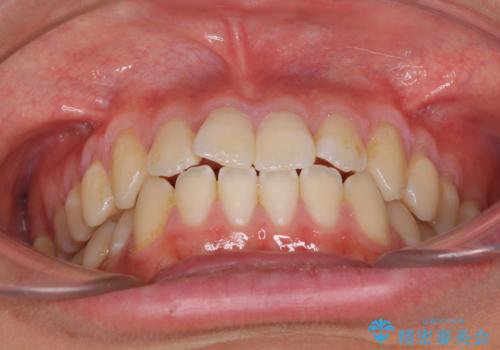

- 上下前歯のデコボコを気にして来院された患者様です。

叢生は軽微であり、費用を抑えて期間もあまりかけずに治療をしたいとのことで、インビザライン・ライトを用いて矯正治療を行うこととしました。